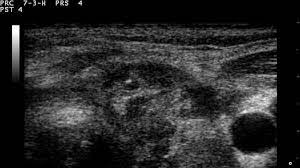

What Does Neck Cancer Look Like On An Ultrasound : Neck Lumps Differential Diagnosis Investigation Teachmesurgery : In the framework of such terms as ultrasound of the neck, can be performed the following studies:. Ultrasound is used to see the thyroid gland and the lymph node of the neck. Fna is generally done on all thyroid nodules that are big enough to be felt. A neck lump or nodule is the most common symptom of thyroid cancer. A lump will form when a cancer cell infiltrates the capsule and multiplies. A nodule or a growth in the thyroid can be seen and identified.

Enlarged Lymph Nodes In Head And Neck Cancer Analysis With Triplex Ultrasonography Sathyanarayan V Siva Bharani K Ann Maxillofac Surg from www.amsjournal.com Ultrasound an ultrasound is sometimes used, especially to look at the thyroid, salivary glands and lymph glands in the neck. Ultrasonography of neck lymph nodes; As thyroid cancer gets more advanced, you might notice symptoms like: Lumps can also form in the lips. A small lump on the neck usually is a lymph node, a small sebaceous cyst or a lipoma, although it could be something else. Reactive lymph nodes look different on ultrasound to lymphoma, so i'm sure the report to the gp will be the same as what she told you. Ultrasound is used to see the thyroid gland and the lymph node of the neck. During biopsy, the ultrasound helps make sure they are getting fna samples from the right areas.

Stage 4 Throat Cancer Life Expectancy Staging Types Risks from post.healthline.com For this scan, you will lie down and a gel will be spread over your neck. Two in three cases of thyroid cancer occur in people under age 55, and 75%. Ultrasound of the thyroid gland. A small lump on the neck usually is a lymph node, a small sebaceous cyst or a lipoma, although it could be something else. The doctor will also inspect the nose, mouth, throat, and tongue for abnormalities, often using a light and a mirror for a. 1 ), and the presence of an echogenic hilus within lymph nodes was previously considered a sign of benignity 44. Unfortunately cancer of the thyroid will not show up on an ultrasound. It is the same type of scan that is performed on pregnant women to view images of their unborn babies.

The sonographer stands facing the ultrasound and uses their right hand to move the transducer on the patient's neck, thus simultaneously facing both the ultrasound monitor ( on the left) and the patient's face ( on the right) figure 4.5. Are there signs of thyroid cancer on ultrasound? Sounds like they've been enlarged from an infection, maybe fighting one you weren't even aware of. A neck lump or nodule is the most common symptom of thyroid cancer. How a nodule looks on ultrasound can sometimes suggest if it is likely to be a cancer, but ultrasound can't tell for sure. Physical examination/blood and urine tests. Skin cancer is by far the most common type of cancer. An ultrasound of the neck is used to examine the carotid arteries located on each side of a patient's neck. The doctor will also inspect the nose, mouth, throat, and tongue for abnormalities, often using a light and a mirror for a. During a physical examination, the doctor feels for any lumps on the neck, lips, gums, and cheeks. Unfortunately cancer of the thyroid will not show up on an ultrasound. Most of the time, patients in the low risk group are simply monitored by ultrasound. An ultrasound scanner uses high frequency sound waves to create images of the internal soft tissues of the face and neck.

Non Thyroid Cystic Masses Identified On Neck Ultrasound from www.healio.com If you have a lump on it. During a physical examination, the doctor feels for any lumps on the neck, lips, gums, and cheeks. Air and bone also reflect sound waves. This means that they are larger than about 1 centimeter (about 1/2 inch) across. A neck ultrasound can be used to observe the thyroid gland to look for nodules, growths, or tumors. Epidemiology it typically presents in younger women with an average age of onset at around 45 y. Ultrasounds are usually quick and most don't require special preparation. The sonographer stands facing the ultrasound and uses their right hand to move the transducer on the patient's neck, thus simultaneously facing both the ultrasound monitor ( on the left) and the patient's face ( on the right) figure 4.5.